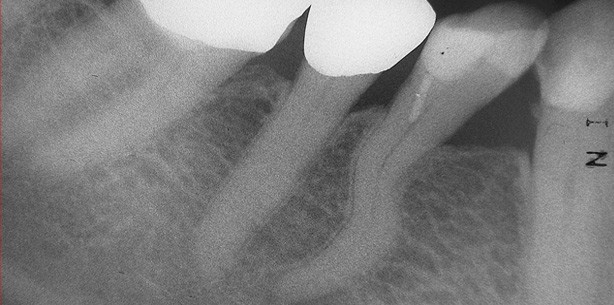

Eine 81-jährige Patientin suchte mit akuten pulpi­tischen Beschwerden im rechten Unterkiefer unsere Praxis auf. Der Vitalitäts-/Sensibilitätstest machte eine stark erhöhte und verlängerte Reaktion am Zahn 45 ­sowie keine Reaktion am Zahn 44 deutlich. Der Perkussionstest zeigte hingegen kein positives Ergebnis am Zahn 45, jedoch eine leicht positive Perkussion am Zahn 44. In der diagnostischen Ausgangsaufnahme war da­raufhin eine deutliche apikale Läsion endodontischen Ursprungs am Zahn 44 zu sehen. Der Zahn 45 blieb ohne pathologischen radiologischen Befund.

Obwohl die apikale Läsion des Zahnes 44 aufgrund der Größe bereits mehrere Monate bestehen musste, war die Ursache des Zahnarztbesuches die akuten ausstrahlenden Beschwerden des Zahnes 45, welcher bereits vor vielen Jahren mit einer Goldkrone versorgt worden war. Die Ausgangsaufnahme (Abb. 1) zeigte weiterhin eine stark gekrümmte Wurzel mit einem s-förmigen Kanalverlauf am Zahn 44. Diese anatomische Besonderheit erschwert die prognostisch sichere apexnahe Aufbereitung des Wurzelkanalsystems erheblich und stellt den Endodontologen vor besondere Herausforderungen. Beide Zähne wurden nach Leitungsanästhesie trepa­niert, die Pulpakammerböden und die Kanaleingänge dargestellt (Abb. 2). Es zeigte sich bei der intrakoronalen Inspektion eine stark verlängerte Blutung aus dem Wurzelkanalsystem des Zahnes 45, während am Zahn 44 eine deutliche Pusentleerung beobachtet werden konnte.